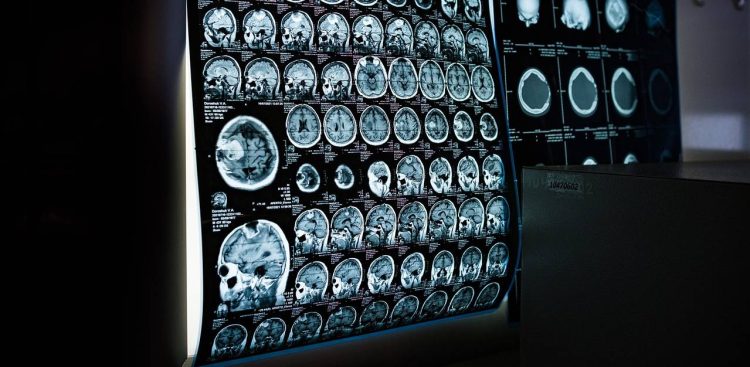

– To urządzenia obejmujące zarówno najnowocześniejsze techniki obrazowania wykorzystywane w diagnostyce, jak i zaawansowane terapie. Oferujemy także różnorodne warsztaty uczące, jak obsługiwać ten sprzęt, jak go wykorzystywać oraz jak łączyć możliwości technologiczne z potrzebami pacjenta. Coraz częściej mamy bowiem do czynienia z osobami z wielochorobowością. Zdarza się, że pacjent trafia na oddział kardiologii zachowawczej, a w trakcie leczenia okazuje się, że wymaga szeregu dodatkowych procedur – wyjaśniała prorektor.